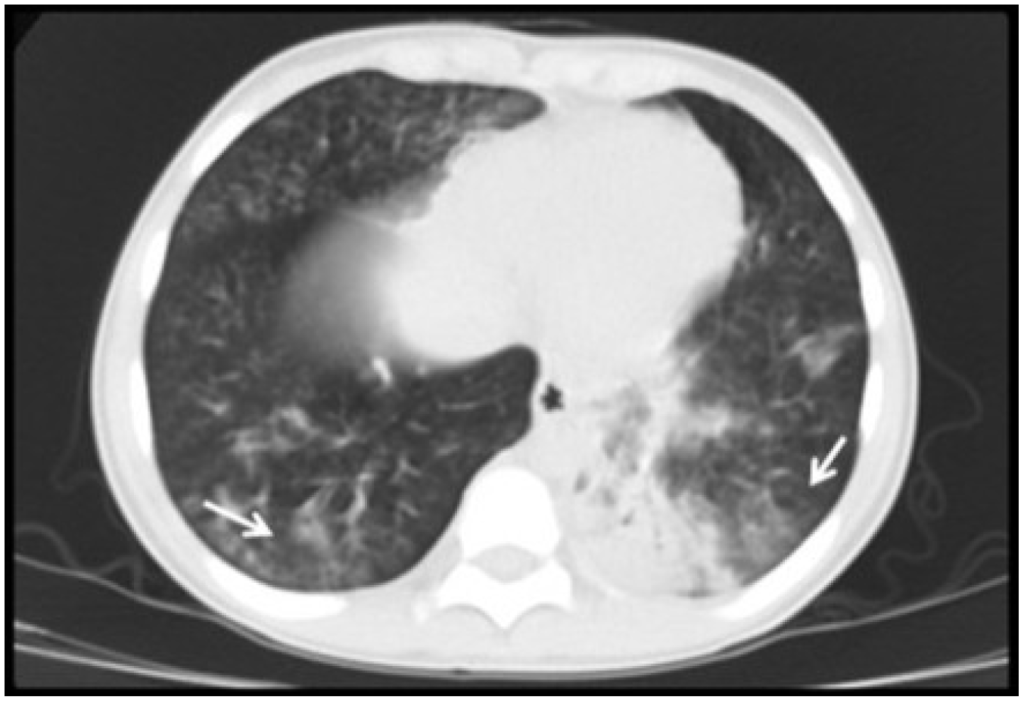

| Radiological variables | |

| Abnormal lung images, n (%) | 15 (100) |

| Ground-glass opacity, n (%) | 12 (80) |

| Consolidation, n (%) | 12 (80) |

| Atelectasis, n (%) | 6 (40) |

| Air trapping, n (%) | 5 (33) |

| Nodular pattern, n (%) | 3 (20) |

| Reticular pattern, n (%) | 1 (6) |

| Tree-in-bud pattern, n (%) | 1 (6) |

3.2. Radiological Findings in CMV Lung Infection